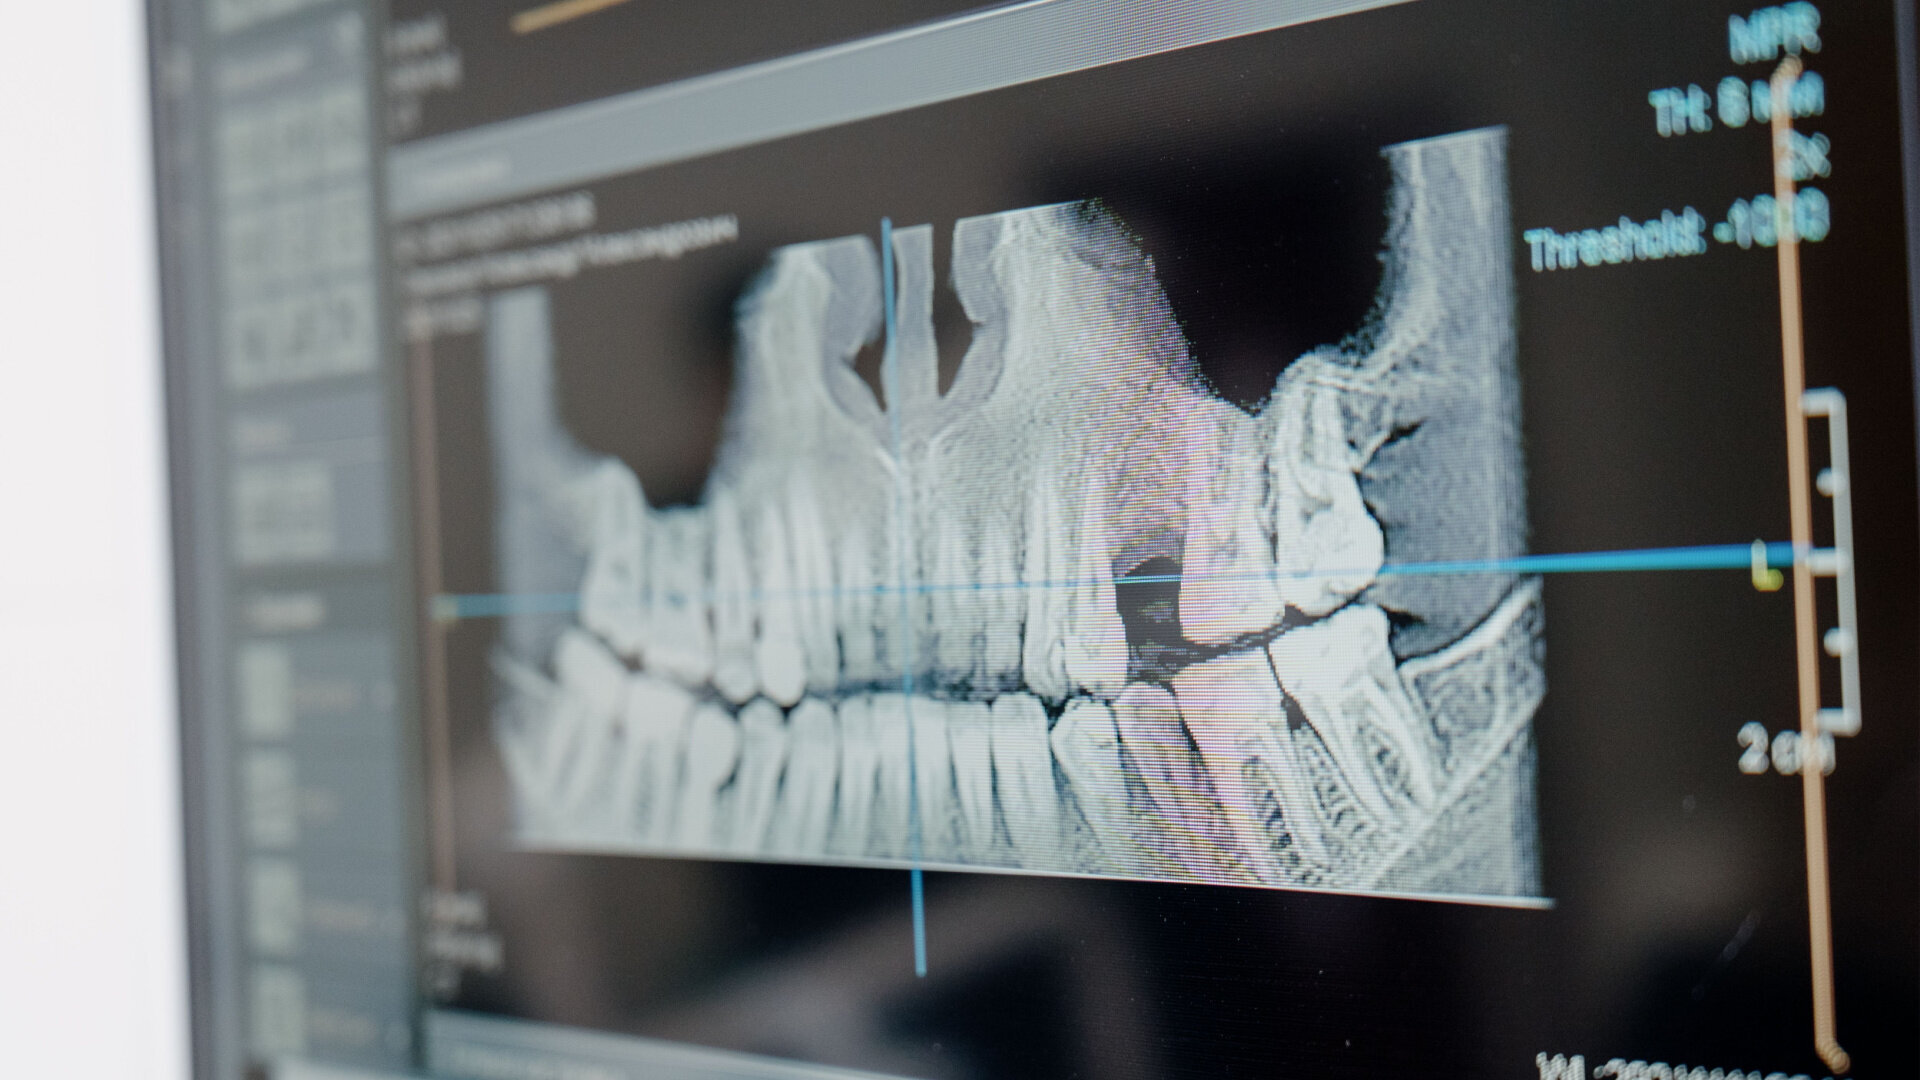

Access our world-class technicians with the most precise dental technology and industry-leading turnaround times.

TopWay integrates innovative technology and manufacturing processes with the most up-to-date dental science to develop dental products that exceed the expectations of dentists and patients.